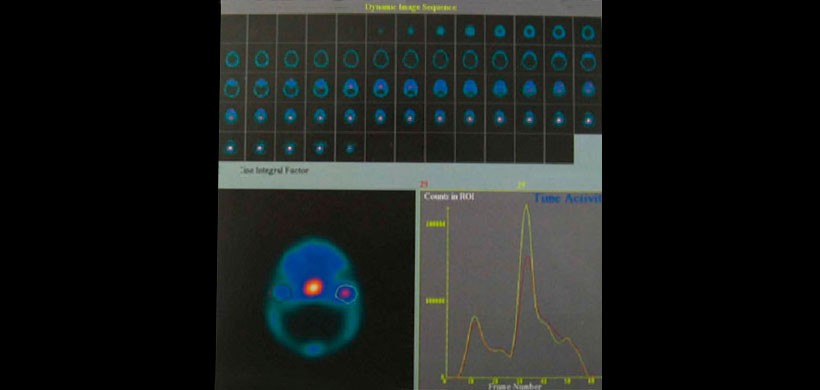

Tomografía Computarizada por Emisión individual de Fotones (SPECT): es una técnica recientemente desarrollada para recoger y desplegar imágenes seriadas por planos paralelos de medicina nuclear. Es una variación de la gammagrafía y consiste en un método de imagenología funcional, que refleja la respuesta metabólica del órgano en evaluación mediante el uso del radiofármaco (Tecnecio 99 MDP), el cual es llevado a un área determinada y controlada por el nivel de actividad metabólica e irrigación sanguínea de la región.

Figura 5: Imagen de SPECT donde se observan diferentes cortes del estudio. La vista axial presenta una mayor marcación en el cóndilo derecho lo cual se asocia con mayor metabolismo óseo en la zona.